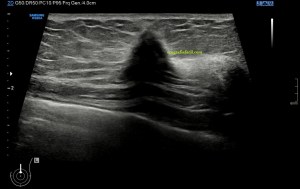

El paciente viene por un bulto en la parte derecha de la espalda, en la región paradorsal alta. Con una sonda de alta frecuencia accedo a la región, que era palpable. Lo primero que observo es que la transmisión del paciente no es buena, esto que a veces pasa que encuentras pacientes, que no sé explicar el motivo, no transmiten bien.

Me da para observar que en la zona de palpación encuentro, profundo en la imagen, un formación hiperecogénica, que está dentro de un músculo. Antes de detallar los hallazgos de la imagen lo que quise fue reconocer bien la anatomía. La piel y el tejido celular subcutánea era muy fácil, también saber que esta anatomía superficial estaba intacta y que la lesión estaba intramuscular, pero me encontraba dos planos musculares, uno superficial, el otro profundo, el profundo con la lesión.

Me tuve que ir al atlas de anatomía para saber cuál era el músculo que estaba debajo del músculo trapecio, que tenía claro que era el superficial. Bien, el músculo que ocupaba el segundo plano en profundidad era el músculo Romboides, que te enlazo para que sepas más de su posición y función.

El protocolo es el típico, cortes en eje corto y largo, con doppler, para comprobar vascularización, como línea roja del lipoma. Imágenes 3,4 y 6.

Después con la radióloga, hicimos una imágenes con «panoramic view» que te dan un detalle de las anatomía con respecto del lado contralateral, sano. Imagen 1.

La lesión era ovalada, hiperecogénica, ocupaba gran parte del músculo, pero respetaba parte de este, que era hipoecogénico (imagen 5), recuerda que así es por definición y que ésta ecogenicidad del músculo es referencia para el resto de ecogenicidades del aparato locomotor. Como te he contado, no había doppler color ni en modo angio.